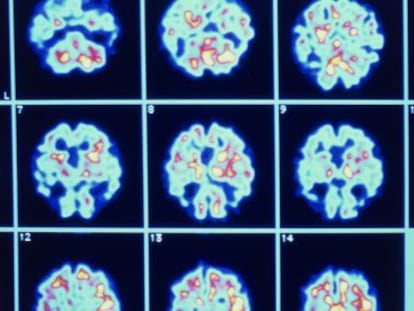

Un nuevo método indica si aparecerá la enfermedad en un año con un simple análisis de sangre El grado de fiabilidad de la prueba desarrollada por investigadores británicos es del 87%

El ensayo se basa en la existencia de 10 lípidos en sangre